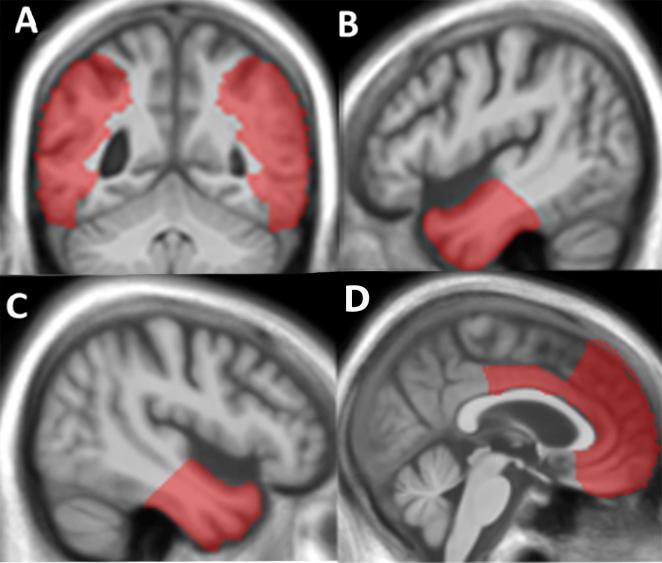

Humour is a complex cognitive and emotional construct that is vulnerable in neurodegenerative diseases, notably the frontotemporal lobar degenerations. However, humour processing in these diseases has been little studied. Here we assessed humour processing in patients with behavioural variant frontotemporal dementia (n = 22, mean age 67 years, four female) and semantic dementia (n = 11, mean age 67 years, five female) relative to healthy individuals (n = 21, mean age 66 years, 11 female), using a joint cognitive and neuroanatomical approach. We created a novel neuropsychological test requiring a decision about the humorous intent of nonverbal cartoons, in which we manipulated orthogonally humour content and familiarity of depicted scenarios. Structural neuroanatomical correlates of humour detection were assessed using voxel-based morphometry. Assessing performance in a signal detection framework and after adjusting for standard measures of cognitive function, both patient groups showed impaired accuracy of humour detection in familiar and novel scenarios relative to healthy older controls (p < .001). Patient groups showed similar overall performance profiles; however the behavioural variant frontotemporal dementia group alone showed a significant advantage for detection of humour in familiar relative to novel scenarios (p = .045), suggesting that the behavioural variant syndrome may lead to particular difficulty decoding novel situations for humour, while semantic dementia produces a more general deficit of humour detection that extends to stock comedic situations. Humour detection accuracy was associated with grey matter volume in a distributed network including temporo-parietal junctional and anterior superior temporal cortices, with predominantly left-sided correlates of processing humour in familiar scenarios and right-sided correlates of processing novel humour. The findings quantify deficits of core cognitive operations underpinning humour processing in frontotemporal lobar degenerations and suggest a candidate brain substrate in cortical hub regions processing incongruity and semantic associations. Humour is a promising candidate tool with which to assess complex social signal processing in neurodegenerative disease.

幽默是一种复杂的认知和情感结构,在神经退行性疾病中很脆弱,尤其是额颞叶变性。然而,这些疾病中的幽默处理很少被研究。在这里,我们使用联合认知和神经解剖学方法,评估了行为变异型额颞叶痴呆患者(n = 22,平均年龄67岁,4名女性)和语义性痴呆患者(n = 11,平均年龄67岁,5名女性)相对于健康个体(n = 21,平均年龄66岁,11名女性)的幽默处理情况。我们创建了一种新颖的神经心理学测试,要求对非语言卡通的幽默意图做出判断,在该测试中,我们正交操纵幽默内容和所描绘场景的熟悉度。使用基于体素的形态测量法评估幽默检测的结构神经解剖学相关性。在信号检测框架中评估表现,并在调整认知功能的标准测量后,两个患者组在熟悉和新颖场景中的幽默检测准确性相对于健康的老年对照组均受损(p <.001)。患者组表现出相似的总体表现概况;然而,仅行为变异型额颞叶痴呆组在熟悉场景中检测幽默相对于新颖场景具有显著优势(p = 0.045),这表明行为变异型综合征可能导致在解码新颖的幽默情境时特别困难,而语义性痴呆会产生更普遍的幽默检测缺陷,这种缺陷延伸到常见的喜剧情境。幽默检测准确性与包括颞顶交界区和颞上叶前部皮质在内的分布式网络中的灰质体积相关,在熟悉场景中处理幽默主要与左侧相关,而处理新颖幽默则与右侧相关。这些发现量化了额颞叶变性中支撑幽默处理的核心认知操作的缺陷,并提出了皮质枢纽区域中处理不一致性和语义关联的候选脑基质。幽默是评估神经退行性疾病中复杂社会信号处理的一种很有前景的候选工具。